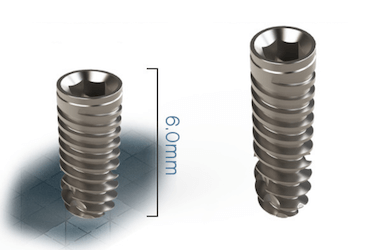

Por último, en el Clínica Dental Guillermo López de Murcia también solemos recurrir a la utilización de microimplantes que son tornillos de titanio con una longitud aproximada de 6mm, especialmente diseñados para los casos de implantología con poco hueso.

Microimplantes para tratamientos de falta de hueso